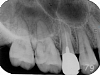

右上顎 詳細画像 (画像をクリックしてください)